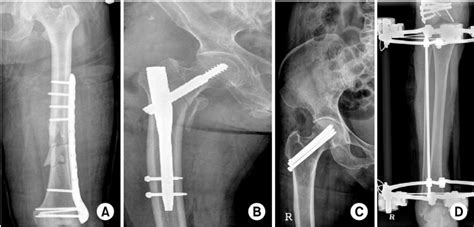

Treatment Options

The treatment of UCL injuries depends on the severity of the injury and the patient’s overall health status. Conservative management, including rest, ice, compression, elevation, and physical therapy, may be effective in treating mild to moderate UCL injuries. However, in severe cases, surgical reconstruction of the UCL may be necessary to restore stability and function to the elbow joint. A thorough evaluation of the patient’s symptoms, medical history, and physical examination findings is essential in determining the most effective treatment plan.